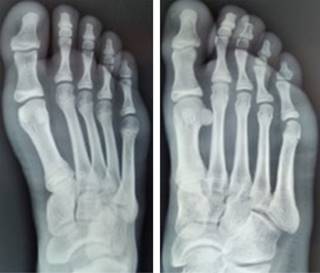

Se realizan radiografías anteroposterior (AP) y oblicua del pie (Figura 1). Se encuentra fractura epifisiaria desplazada de la cabeza del segundo metatarsiano.

Figura 1: Radiografías anteroposterior y oblicua del pie derecho, en la cual se encuentra fractura desplazada de la epífisis del segundo metatarsiano.

Figura 2: Radiografías anteroposterior y oblicua del pie derecho, posterior a reducción cerrada. Se muestra adecuada reducción de fractura epifisiaria del segundo metatarsiano.

Figura 3: Radiografía anteroposterior de pie a 36 meses de la fractura. Se observa adecuada reducción y sin complicaciones a largo plazo.